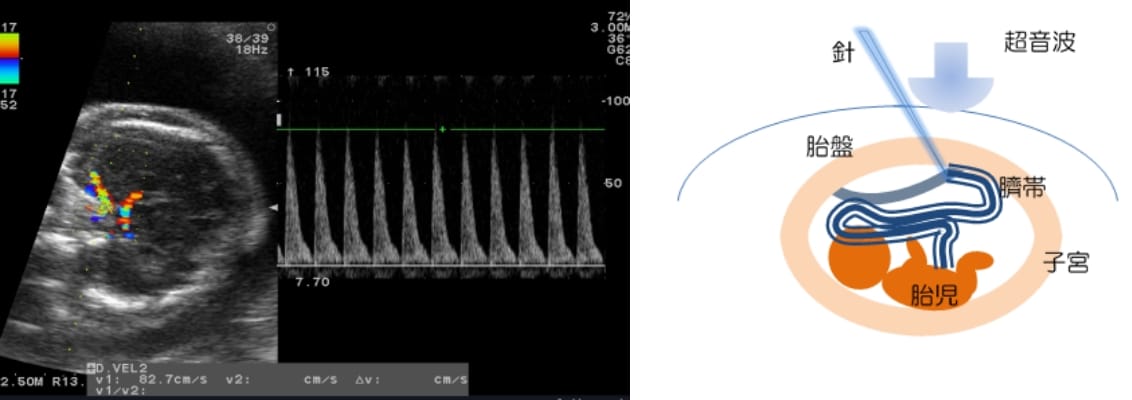

胎児輸血

おなかの中の赤ちゃんも、さまざまな原因によって貧血になることがあります。大人の場合、血液検査によって貧血があるかどうか調べますが、おなかのなかの赤ちゃんも基本的には同じ血液検査で調べます。超音波で確認しながら、お母さんのおなかを通して針を刺し、臍帯から血液をとります。これは簡単なことではありません。そのため最近では、治療を必要とする貧血があるかどうかを、超音波検査で推測する方法が知られています。赤ちゃんの頭の中大脳動脈という部分の血流速度を測る方法です。超音波検査で胎児貧血が疑われた場合、臍帯穿刺を行い、臍帯血の採血をして確認します。

超音波で臍帯静脈の位置を確認しながら、採血に使う細い針を用いて、臍帯静脈を穿刺し、輸血を行います。貧血の原因によっては、何度か輸血を繰り返すこともあります。